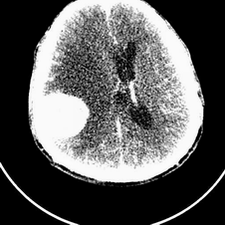

标题: CT25808:男,48岁,头痛多年,近段时间头痛加重伴步态不稳 [打印本页]

标题: CT25808:男,48岁,头痛多年,近段时间头痛加重伴步态不稳

平扫:右颞顶叶病灶呈等低密度伴大面积水肿,脑室受压变形。增强:病灶显著强化。考虑淋巴瘤或黑色素瘤。

1)不排除黑色素瘤可能;建议行mri检查。2)大脑镰下疝。3)脑积水(梗阻性)。